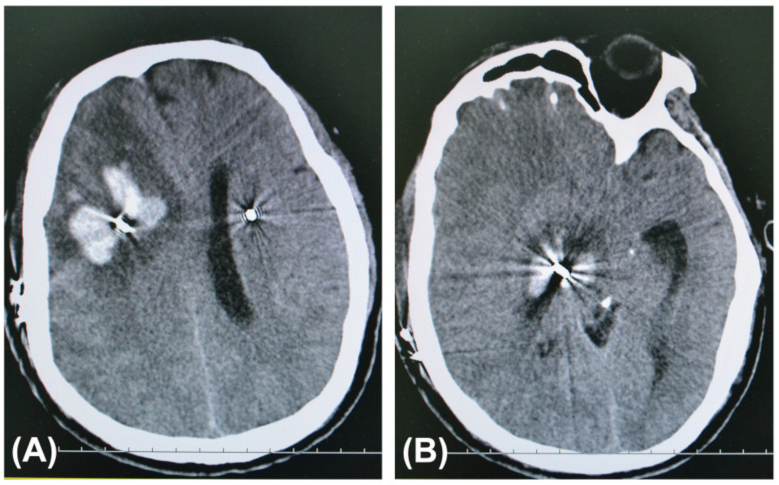

Statistically significant differences in the numbers of both patients and leads associated with symptomatic ICH were observed between the trajectory planning group and the non-trajectory planning group (p < 0.05). No symptomatic ICH patients had microelectrode recordings (MER), which were seldom used in this series. All bleeding cases were PD patients with the STN as their targets. The details of the patients with symptomatic ICH in the non-trajectory planning group were published in our previous article []. In the trajectory planning group, two patients developed asymptomatic ICH as observed on routine postoperative CT images. In the non-trajectory planning group, regular postoperative imaging was not performed in 186 patients, whose cranial CT scan was not performed on the first day after operation. The symptomatic ICH cases after DBS surgery in the two groups are shown in Table 3. CT images of a PD patient with symptomatic ICH after DBS surgery in the non-trajectory planning group are shown in Figure 1.

Figure 1.

Axial computed tomography (CT) slices at the hemorrhage sites taken after the health of a 53-year-old man with PD in the non-trajectory planning group deteriorated on the 6th postoperative day. He had suffered from a headache for a few days before falling into a coma. His hematomas were along the trajectory of the definitive electrode in the right frontal lobe (A), basal ganglia, and midbrain (B).